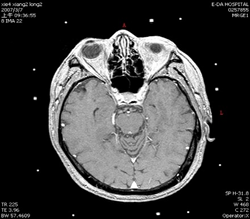

聽神經瘤

手術前

手術後